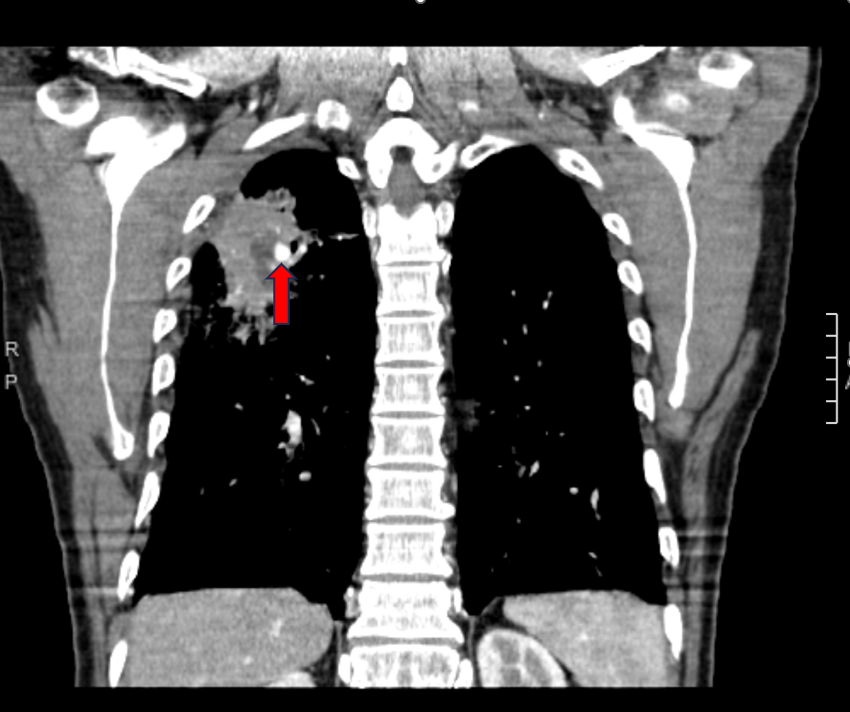

術(shù)前圖片:(紅色箭頭處為肺動(dòng)脈假性動(dòng)脈瘤)

術(shù)后復(fù)查胸部CT增強(qiáng):動(dòng)脈瘤瘤體消失。